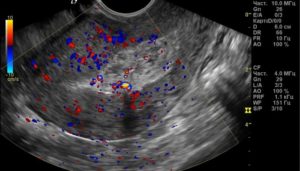

- Эндометрия (его толщину: слой более 26 мм требует оперативного вмешательства; наличие образований, в том числе остатки плодного яйца: на УЗИ – темное круглое образование в толще слоя).

- Миометрия (однородность, отсутствие образований – при патологии на мониторе одиночные и множественные темные пятна).

Проводится визуальный осмотр шейки матки и пальпация. Внутренний зев ее будет расширен, плодный остаток в наличии. УЗИ определит его объем и локализацию, а также общее состояние репродуктивных органов. Биохимический анализ крови расскажет о функционировании органов и систем пациентки.